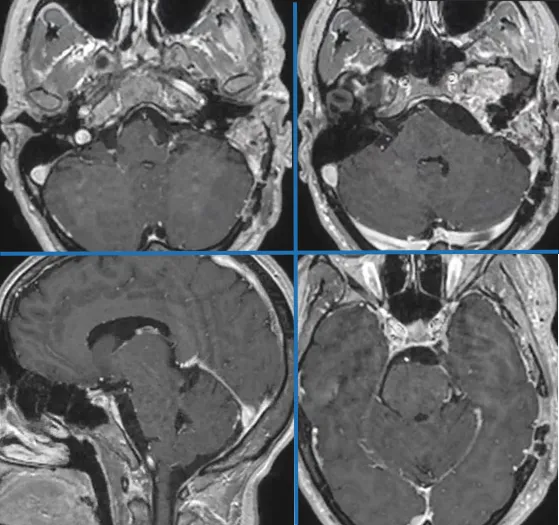

肿瘤切除在多视角下于蛛网膜下腔内精细进行,通过锐性解剖以全切梅克尔腔等处的肿瘤,并全程注重保护第IV、VI颅神经及下组颅神经。最终,使用帽状腱膜移植物与腹部脂肪严密修补硬脑膜缺损,完成骨瓣复位固定,肿瘤得到顺利切除。

术后MRI

这个案例只是INC国际教授手术中一个常规案例,与福教授同台的国内神经外科专家这样评价他的手术: